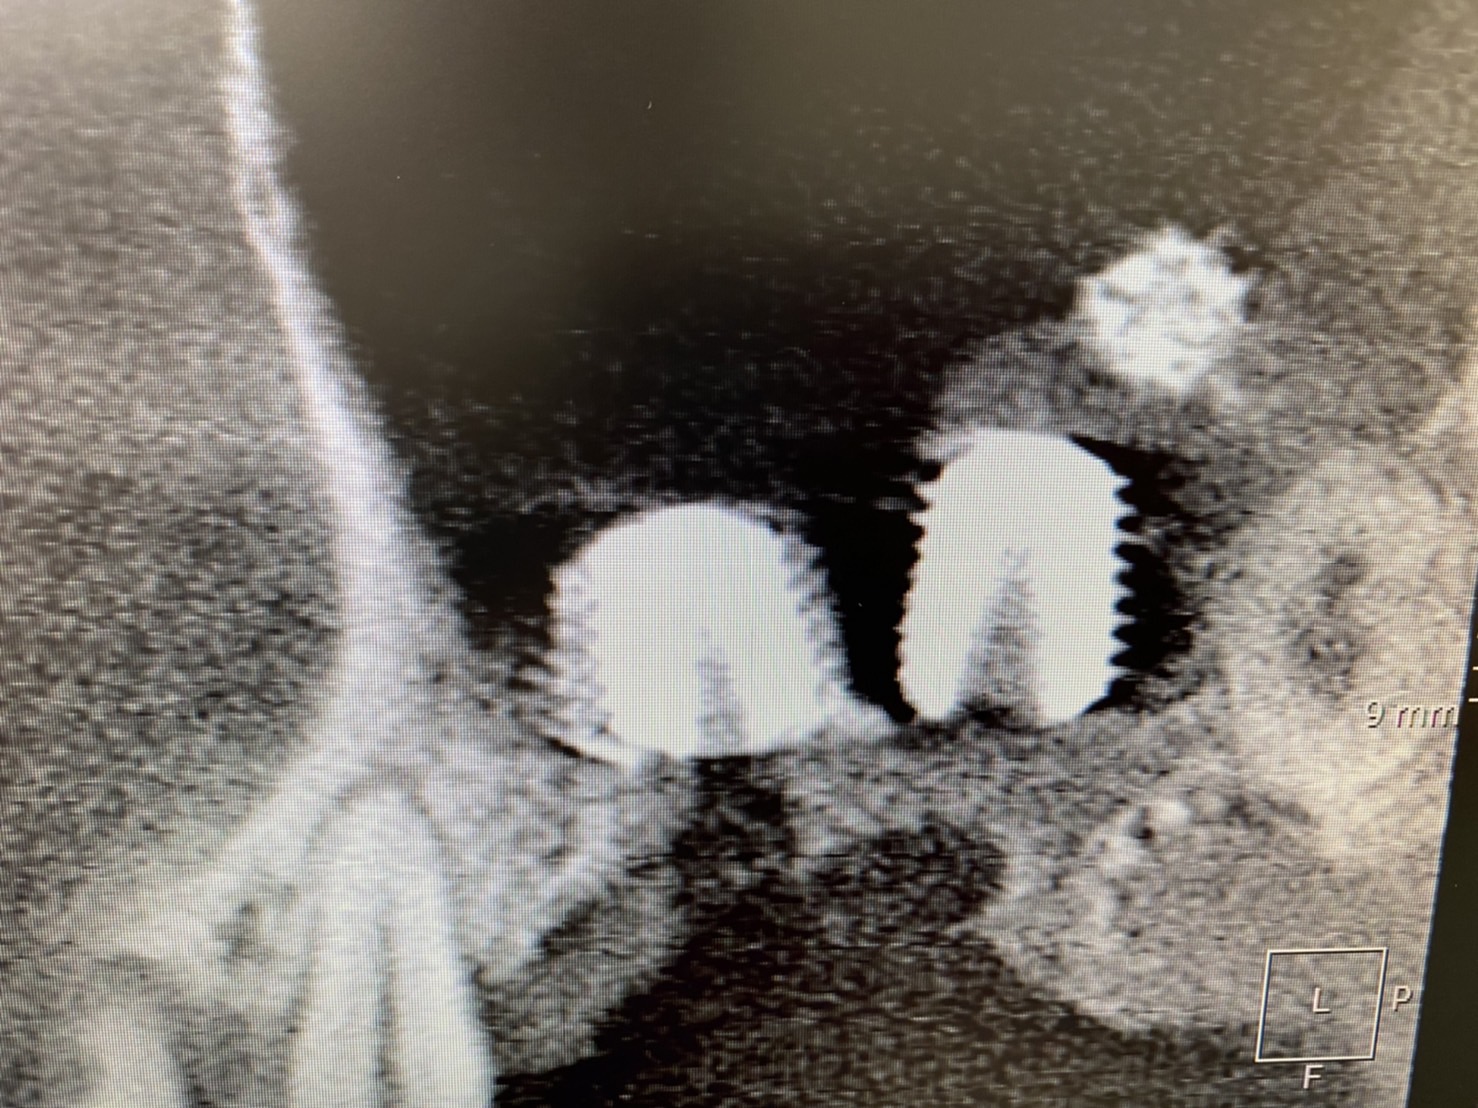

5ヶ月前に、左上ソケットリフト併用のインプラントオペをされた方の経過

(今年7月20日ブログ掲載)

残存骨0.5〜1mmしかなく、、

1次オペ後、5ヶ月待って本日2次オペを!

I SQ値も良く、一安心!